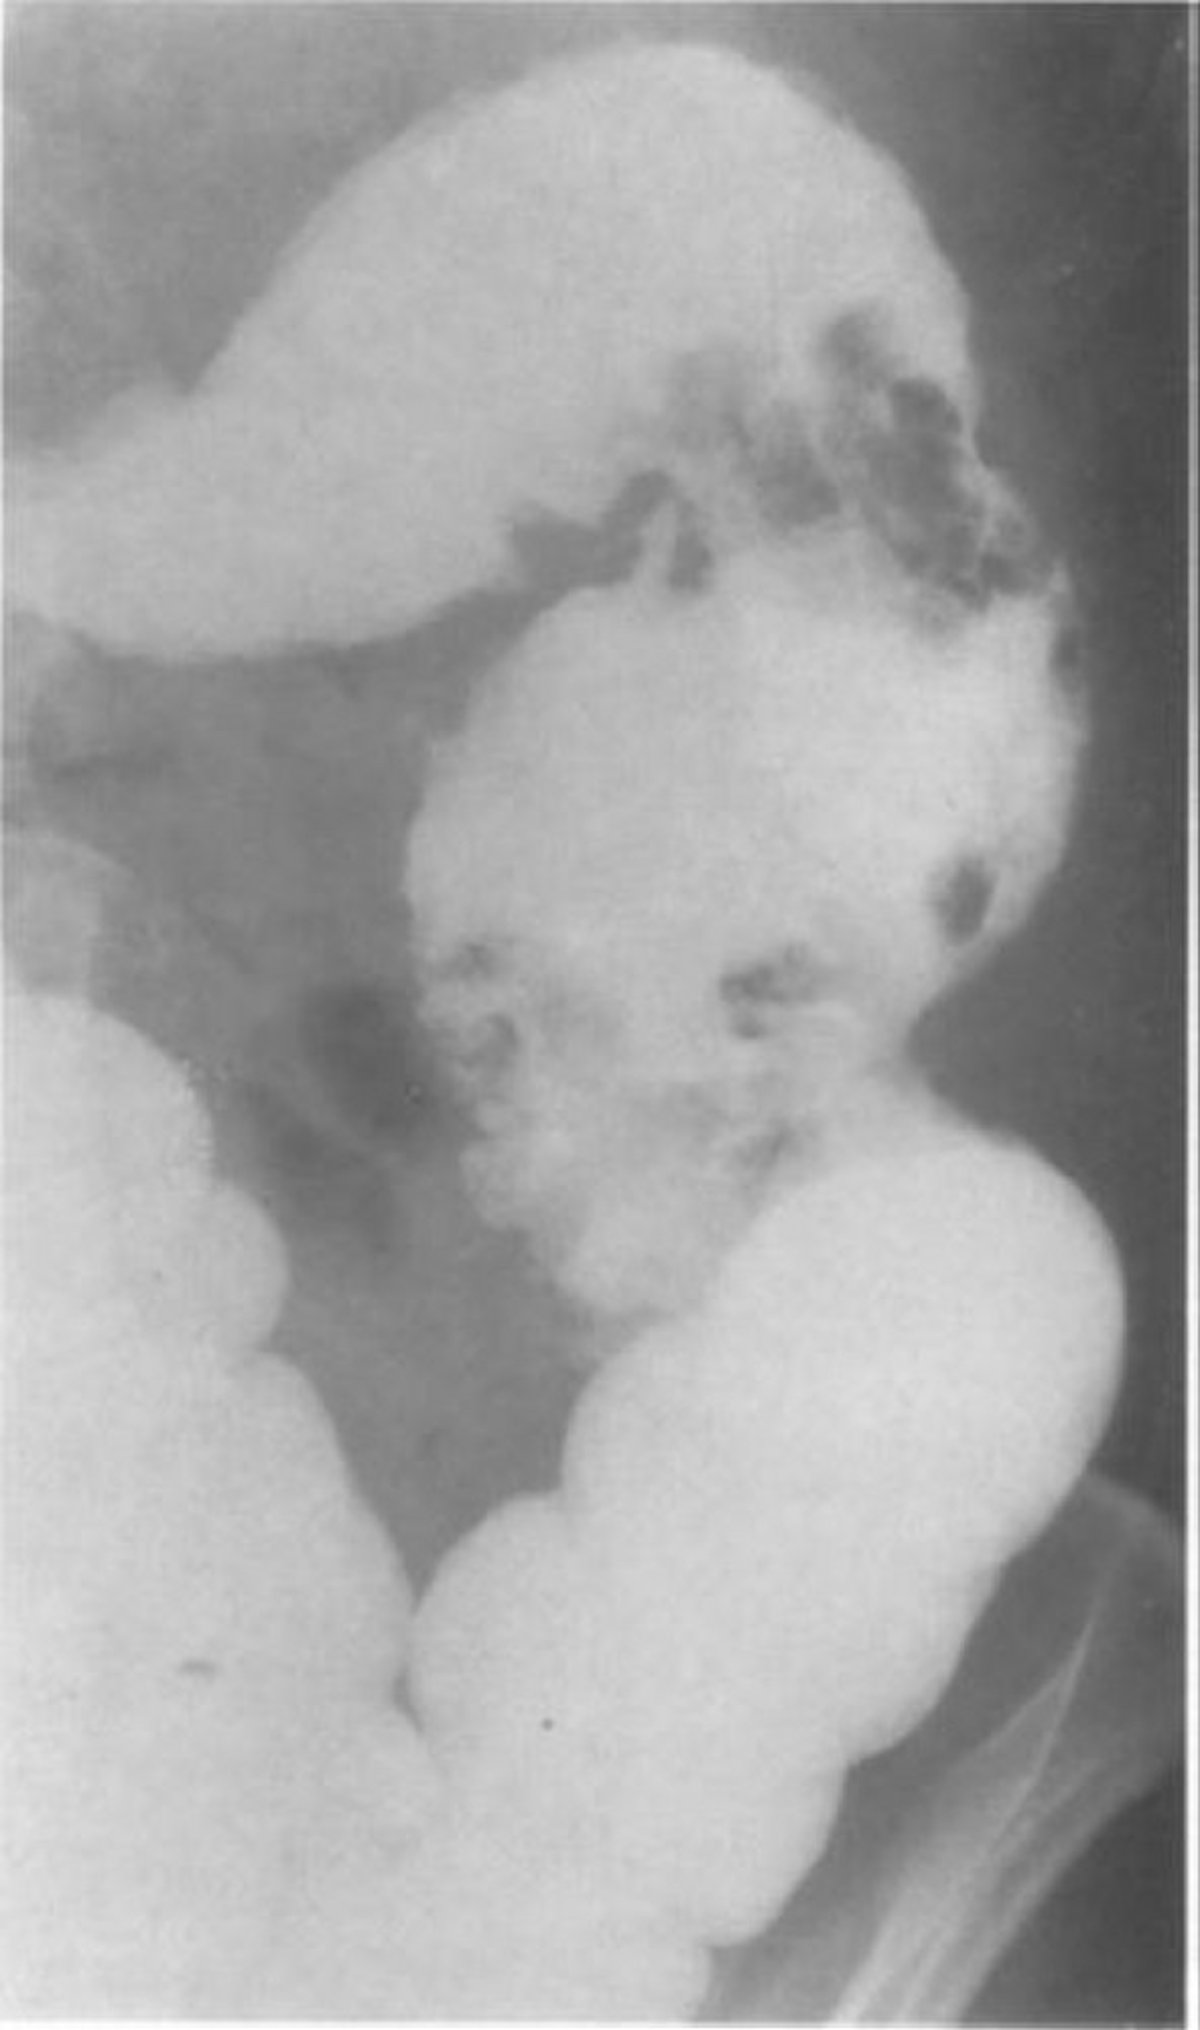

Barium Enema Showing Mucosal Pseudopolyps

This image of a patient with granulomatous colitis shows 2 clusters of large pseudopolyps in the descending colon.